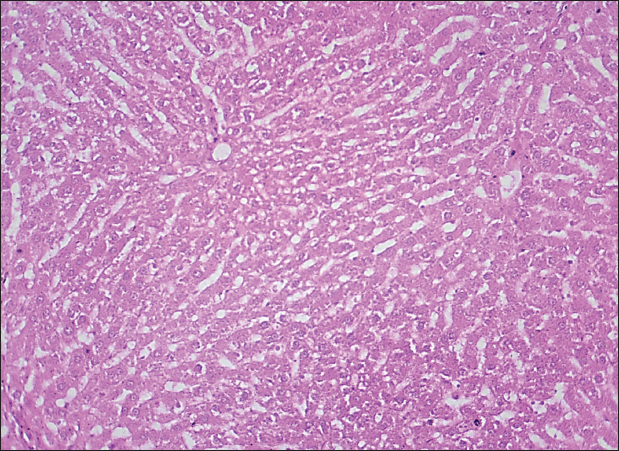

Fig. 1. Histological section of liver in rats of the control group. The section shows a normal histological structure for the hepatic sinusoid without any significant occupied lesion (H and E stain 100X).

Fig. 2. Histological section of liver in rats drenched with 0.6 mg/kg citalopram and treated with 10 mg/kg J. regia pulp extract. The section shows the normal histological structure of hepatic tissue without any significant occupied lesion (H and E stain 100X).

Fig. 3. Histological section of liver in rats drenched with 0.6 mg/kg citalopram and treated with 20 mg/ kg J. regia pulp extract. The section shows the normal histological structure of hepatic tissue without any significant occupied lesion (H and E stain 100X).